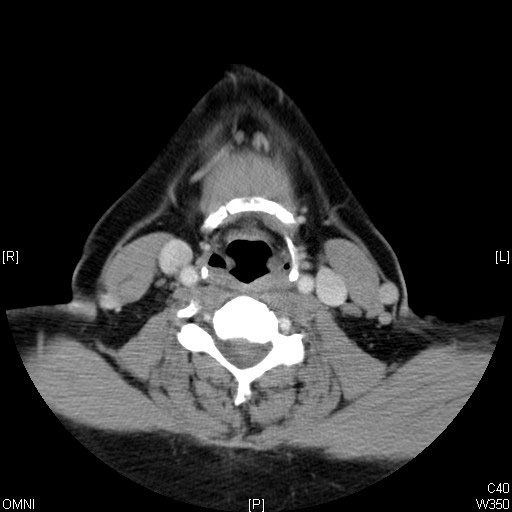

Identify Pyriform sinus and Hyoid